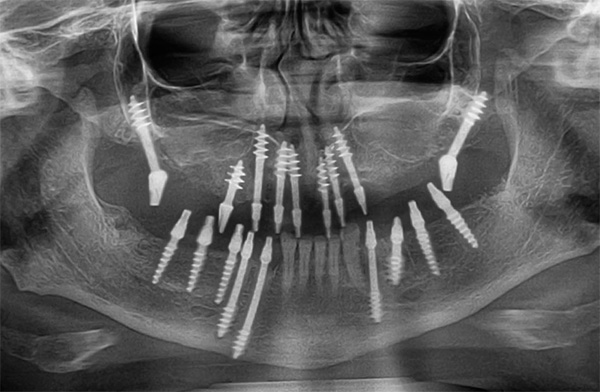

O período médio de enxerto de implante é de cerca de 2-4 meses na mandíbula inferior e cerca de seis meses na parte superior. Essa diferença se deve ao fato de os ossos da mandíbula serem melhor supridos com sangue, geralmente são maiores e mais fortes, com maior carga mastigatória. Além disso, o seio nasal está localizado acima do tecido ósseo da mandíbula superior, cuja proximidade costuma trazer dificuldades adicionais ao instalar implantes.

A osteointegração (um termo médico para o processo de fusão de raízes metálicas com o maxilar) começa imediatamente após a instalação das estruturas. O momento do enxerto depende em grande parte do estado inicial do osso maxilar, bem como da qualidade de fabricação e do modelo do implante.

Nesse caso, o método pelo qual os implantes foram instalados na mandíbula não desempenha um papel especial. Independentemente de os implantes serem carregados imediatamente (por exemplo, com implantação basal) ou somente após a fusão completa com o osso - em ambos os casos, o momento do enxerto não difere muito.